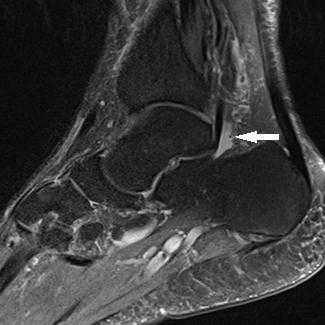

Прежде всего, это боль по задне-внутренней поверхности голеностопного сустава. Возможно «защёлкивание» большого пальца при его сгибании. Хруст, крепитация по задне-внутренней поверхности голеностопного сустава при активных движениях. При физикальном осмотре определяется боль при сгибании большого пальца через сопротивление, при форсированном подошвенном сгибании в голеностопном суставе, при этом боль отсутствует в области первого плюсне-фалангового сустава. Для диагностики повреждения сухожилия длинного сгибателя большого пальца стопы целесообразно выполнение МРТ, при этом обнаруживается скопление жидкости вокруг сухожилия на уровне голеностопного сустава, изменение сигнала от самого сухожилия.

При разрывах сухожилия длинного сгибателя большого пальца помимо остро возникшей боли и отёка по задне-внутренней поверхности голеностопного сустава определяется выраженная слабость подошвенного сгибания большого пальца стопы.